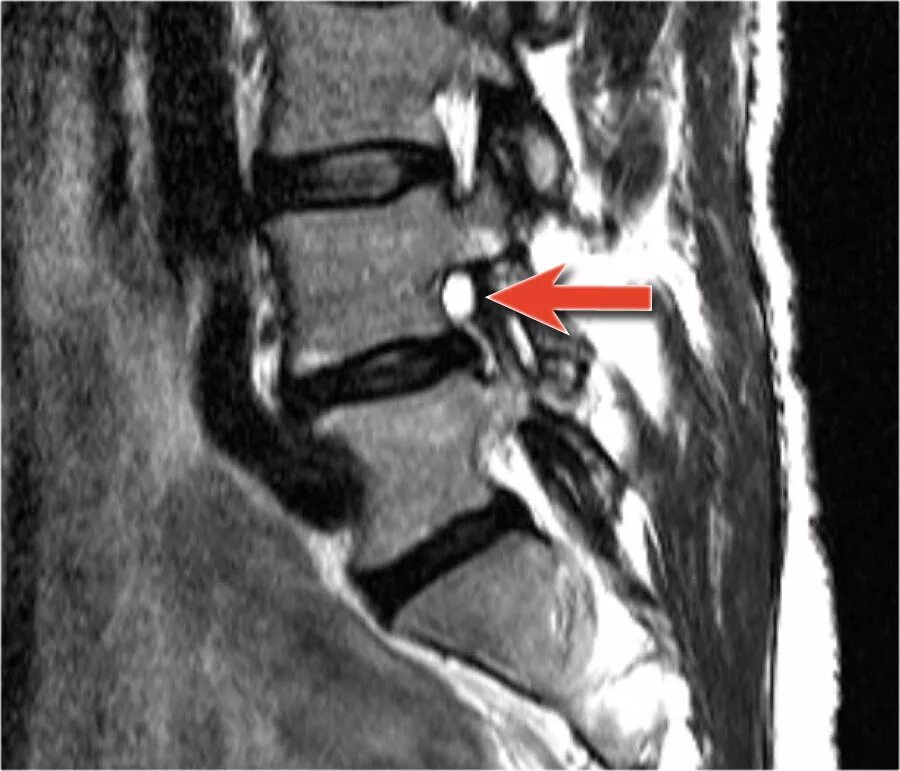

Киста в грудном отделе позвоночника